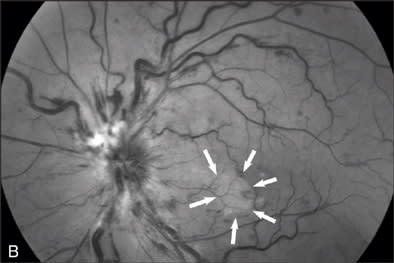

At our initial examination in August 2008, corrected visual acuity was 20/30 in the right eye and 20/50 in the left, with normal ocular pressure in both eyes. There were no rubeosis irides in either eye. Fundus examination appeared normal in the right eye while the left eye revealed a typical nonischemic CRVO (Figure 1A). Fluorescein angiography of the left eye (Figure 1B to 1E) showed generalized dilated, tortuous retinal veins, intraretinal hemorrhages, peripheral retinal non-perfusion areas, and microvascular leakage at the macula (Figure 1E, arrow). Despite the peripheral retinal ischemia, the macula itself was not ischemic at the first visit, as evidenced by the early phase FA showing 2 cilioretinal arteries supplying the fovea (Figure 1C, arrow). Spectral domain OCT (OPKO-OTI, Miami, FL.) confirmed the diagnosis of cystoid macular edema (CME). The patient got intravitreal bevacizumab (Avastin) injection (1.25 mg/0.05 mL) at the first visit.

At the 5-month follow-up visit in February 2009, corrected visual acuity remained 20/20 in the left eye, with normal ocular pressure in both eyes. There were no rubeosis irides in either eye. Fundus examination appeared normal in the right eye with improvement in the appearance of the retinal vasculature in the left (Figure 2A). Fluorescein angiography of the left eye (Figure 2B to 2E) showed resolution of the CRVO characteristics (dilated, tortuous retinal veins, intraretinal hemorrhages, peripheral retinal non-perfusion areas) with no microvascular leakage at the macula. Spectral OCT confirmed no cystoid macular edema (Figure 2E).